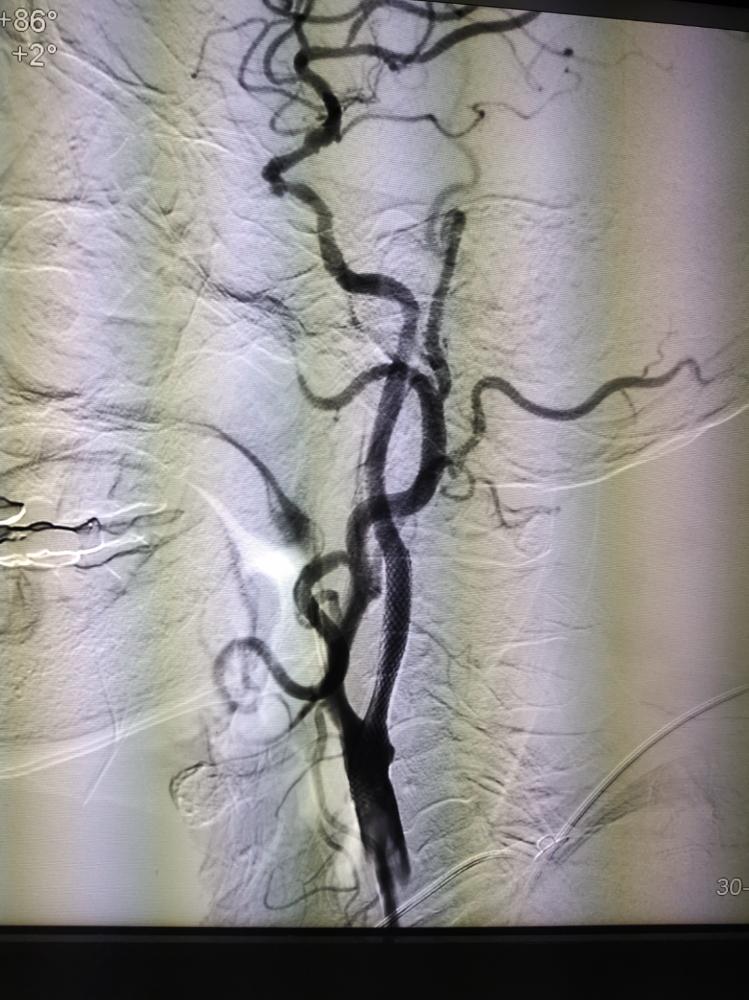

01脑血管造影术(DSA)

脑血管造影术(DSA):是目前最准确的脑血管检查方法,分辨率最高,是诊断脑血管疾病的“金标准”。缺点是需要进行动脉插管,有微小创伤。在临床实践中,如果通过彩超、MRA或CTA检查,考虑有脑血管疾病的情况,特别是需要进一步介入治疗的时候,需要通过DSA检查最后明确诊断。

02颈动脉狭窄介入术(CAS)

颈动脉狭窄介入术(CAS):是治疗颈动脉狭窄的经典的治疗方式,手术中医生将指引导管到位后,将微导丝小心通过患者颈动脉狭窄病变处,再沿细导丝用不同球囊扩张颈动脉的狭窄区域,然后在后期置入颈动脉的支架来控制这个狭窄的弹性回缩或者夹层,维持持续的血运。一般推荐在整个治疗过程中使用远端的栓子保护装置,就是脑保护伞,这个脑保护伞是在我们导丝、导管通过病变以后,置入到病变的远端,在球囊扩张的过程中和支架置入的过程中,在病变的远端进行血栓的过滤。栓子保护装置的使用大大降低了手术并发症的发生率。

03机械取栓术

机械取栓术:通过股动脉穿刺,把取栓的器械通过血管内到达血管闭塞的位置,然后穿过闭塞血管,通过取栓的器械或出栓的导管把血栓取出,使血管血流得以恢复的技术方法。机械取栓能够让90%以上的血管得以再通,机械取栓比静脉溶栓能让血流的再通率大幅度的提高。脑缺血进行性加重,可能导致重度残疾或危及生命,如果在时间窗内尽早的开通血管,能较大幅度的降低致残率或致死率。时间窗:前循环6-8小时,后循环24小时内。